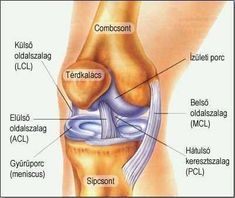

Ujjainkban ugyanis csak inak és ízületek vannak, a fájdalom ezek betegségére utal. Ennek többféle oka lehet a reumától a különböző gyulladásokon át egészen az autoimmun betegségig.

Az egyik elsődleges ok az ujjfájdalmaknak az ínhüvelygyulladás, amely nemcsak fájdalommal jár, hanem az ujj megdagadásával és merevvé válásával is. A gyógyszeres kezelés mellett ilyenkor érdemes egyáltalán nem mozgatni az ujjakat, ami azonban elég nehezen megoldható a mindennapokban.

Az oszteoartrózis az ujjak deformitását okozza, ráadásul nagy fájdalommal jár. Kemény ízületi ízületi ujjak jelennek meg az ujjakon, amelyek fel is dagadhatnak. Az ujjak mellett a bőr is pirossá, érzékennyé válhat.

A kezelés rendkívül összetett, a gyulladáscsökkentő gyógyszerek mellett gyógytorna is szükséges, súlyos esetben ízületi ízületi ujjak műtét is várhat az érintettre. Ez akadályozza az ujjak mozgását és fájdalommal jár.

Hátterében általában ízületi gyulladás áll. Az érintett így képtelen ökölbe szorítani a kezét, és finommozgásokat sem tud produkálni. Ennek oka általában szintén ízületi gyulladás, de következménye lehet rosszul gyógyult törésnek, ficamnak is.